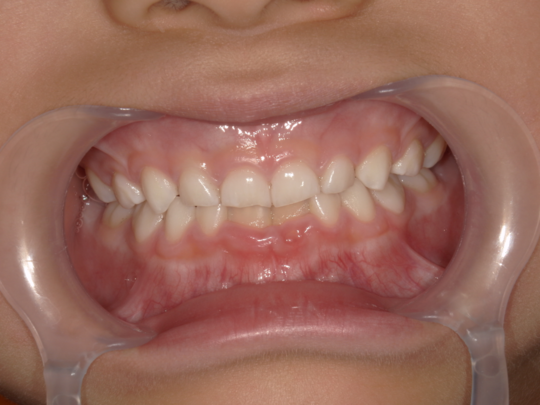

治療前

治療説明 歯科矯正で取り外し可能な矯正方法である床矯正で治療しました

治療期間 4年

治療費用200000 円

治療後

治療の副作用(リスク)歯の動き方には個人差があり、予想された治療期間が延長する可能性があります。。床矯正の使用状況、矯正歯科治療には患者さんの協力が必要であり、それらが治療結果や治療期間に影響します2次矯正が必要になる場合もあります。